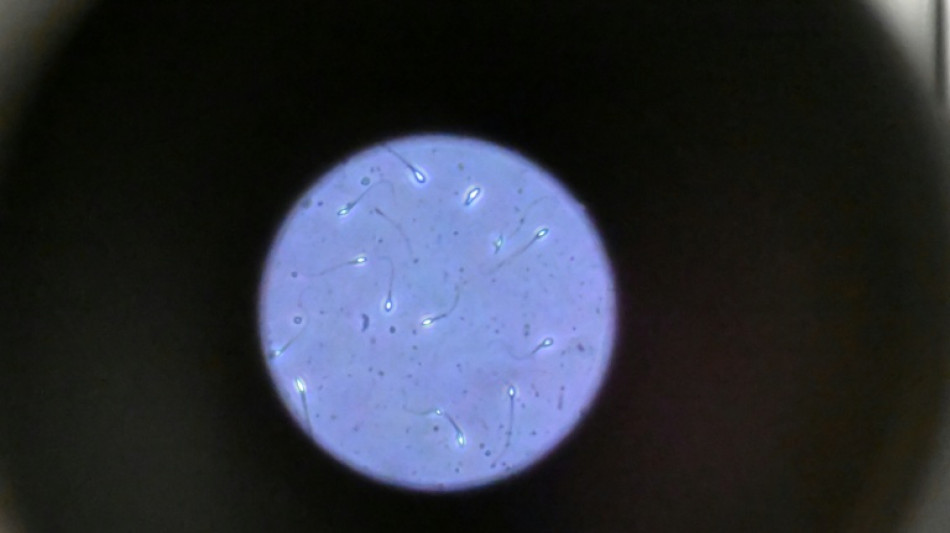

Dans l'espace, les spermatozoïdes ont du mal à trouver leur chemin / Photo: Damien MEYER - AFP/Archives

Dans l'espace, les spermatozoïdes ont du mal à trouver leur chemin vers l'ovule en raison de la microgravité, qui perturbe aussi le développement des embryons, selon une étude publiée jeudi dans Communications Biology.